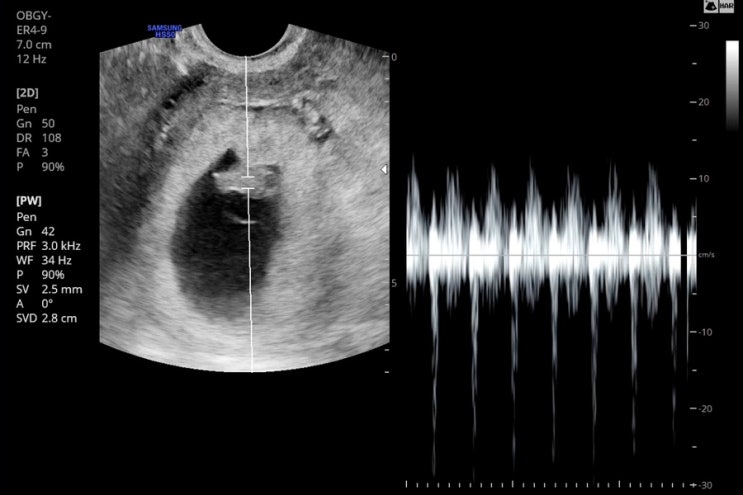

생리일로 봤을땐 12월14일이였고 5주 아기집크기로는 12월12일 7주 검진때 12월15일 9주검진때 12월17일 출...

두번째이야기) 7주 초음파 보고온 날

나는 동탄 제일병원으로 진료를 다니고 있고 첫째 하원시간이 빨라서 오전밖에 진료를 볼 수가 없는 상황인...